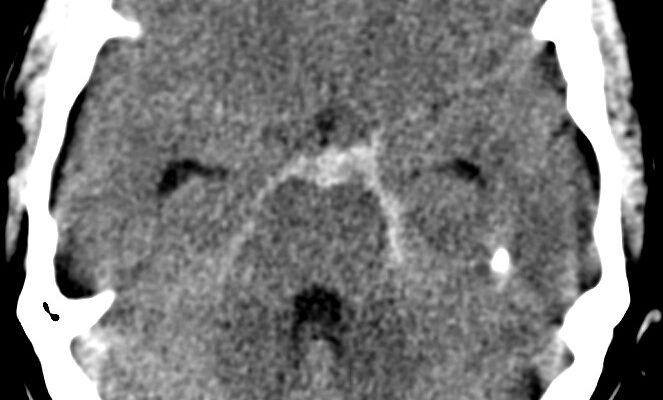

Субарахноїдальний крововилив: наслідки Субарахноїдальний крововилив (СК) — це серйозний стан, який вимагає негайної медичної уваги. Але що ховається за